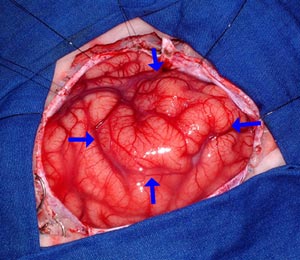

Figura 43 - Fotografia realizada durante a cirurgia.

Figura 50 - Fotografia realizada durante a cirurgia.

Figura 53 - Fotografia intra-operatória.